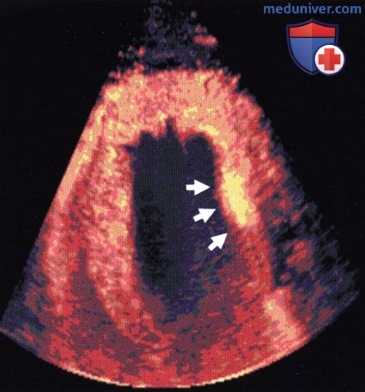

Маркировка статичных лейкоцитов в сердце свиньи через 20 мин после инъекции. Контрастное средство обнаруживается только в миокарде (стрелки: очаг постишемического воспаления).